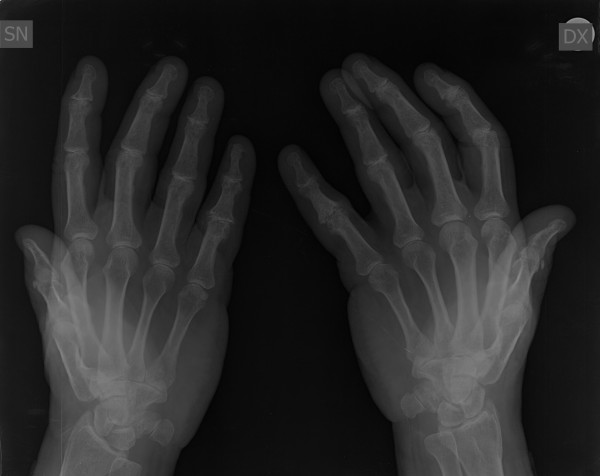

Mi piacerebbe avere un ulteriore parere sulla radiografia alle mani che allego anche per una eventuale cura da seguire. Grazie!!

Non ha senso un parere del reumatologo quando esiste un referto del radiologo. Il problema potrebbe nascere se il quadro clinico e/o di laboratorio fossero in disaccordo con i dati radiologici. E' solo dal confronto dei 3 elementi (clinico in primis, poi radiologico e di laboratorio) che si può azzardare una diagnosi e quindi impostare un trattamento. Le macchine finora non sostituiscono del tutto il medico.